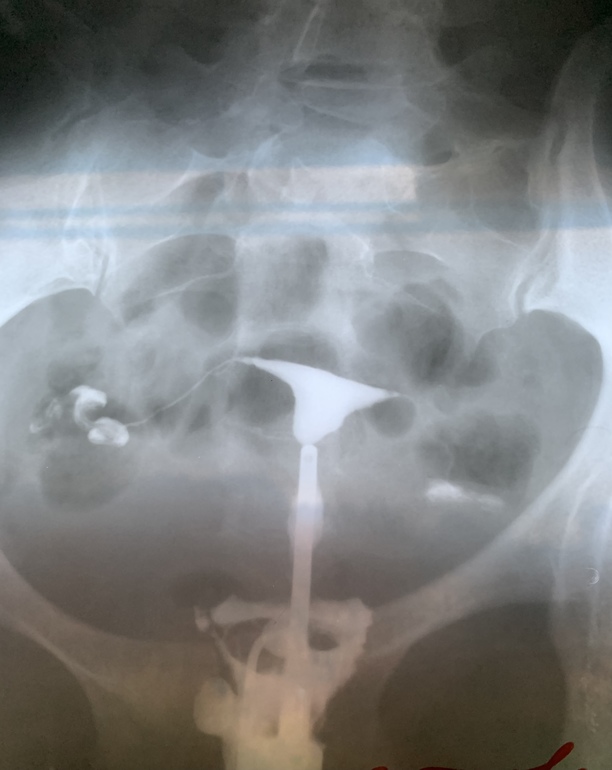

Снимки ГСГ, интерпретация результата

Девушки, привет! Выписалась я из больницы счастливая, обе трубы проходимы. Врач рассказала, о том что ГСГ чудодейственная процедура, которая имеет промывающий эффект. То есть от нее промываются мелкие спайки. И многие беременеют в первых циклах после ГСГ. Я с этими снимками еду к своему репродуктологу. А она говорит, что трубы проходимы лишь частично, что мало контраста проникло в брюшную полость. Сказала, если к весне не удастся забеременеть, отправит на лапароскопию...